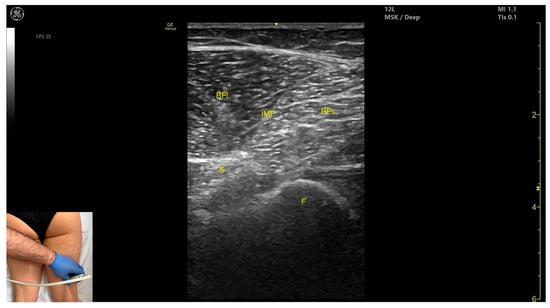

3.11. Biceps Femoris (BF)

3.11.1. Overview

3.11.2. Ultrasound Identification

3.11.3. Key Ultrasound Landmarks

- Muscle morphology: It has two heads: the long head (medial) and the short head (lateral), which can be approached individually, separated by an intramuscular fascia.

- Muscle position: It appears as a superficial muscle mass and is the most lateral muscle in the posterior (flexor) compartment of the thigh at this level. The long head lies adjacent to the sciatic nerve, which runs underneath the muscle.

- External fascia: A pronounced fascia separates the BF from the subcutaneous plane, and from the vastus lateralis and semitendinosus, which is relevant during BoNT-A injections.

- Dynamic evaluation: During dynamic evaluation, scanning proximally toward the hip joint, the long head increases in thickness while the short head decreases. At the mid-thigh, the short head disappears, and the long head reaches its maximum thickness. Scanning distally toward the knee joint, the short head increases in thickness, and the long head decreases. Muscle contraction is visible during hip extension, external rotation, knee flexion, and the external rotation of the leg.

3.11.4. Clinical Implications and Injection Strategy

- 15–30% of the reference line for the short head;

- 50–60% of the reference line for the long head.

- For the short head, the transducer is placed transversely on the distal third of the posterior-lateral thigh;

- For the long head, the transducer is placed transversely at mid-thigh level on the posterior-lateral thigh.